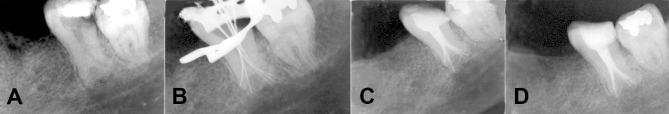

A 28-year old patient was referred for endodontic treatment of his left mandibular second molar. The patient had no history of systemic diseases and his chief complaint was spontaneous pain in left posterior region of mandible. Clinically, there was a deep caries in the left mandibular second molar. Radiographic examination of this tooth revealed a long crown containing large pulp chamber and two short roots with a apically located furcation, indicating hypertaurodontism. After coronal access preparation, five orifices were found including mesiolingual, mesiobuccal, distobuccal, mid-distal and distolingual. Subsequent to root canal preparation, a modified filling technique was used for canal obturation. After one year the treated tooth was symptom free.

一名28岁患者因左下颌第二磨牙接受根管治疗而前来就诊。该患者无全身疾病史,其主要诉求是下颌左侧后部自发疼痛。临床上,左下颌第二磨牙有深龋。对该牙进行的影像学检查显示,牙冠长,髓腔大,两根短,根分叉位于根尖,提示牛牙样牙。开髓后,发现五个根管口,包括近中舌侧、近中颊侧、远中颊侧、远中中部和远中舌侧。根管预备后,采用改良充填技术进行根管充填。一年后,治疗的牙齿无症状。